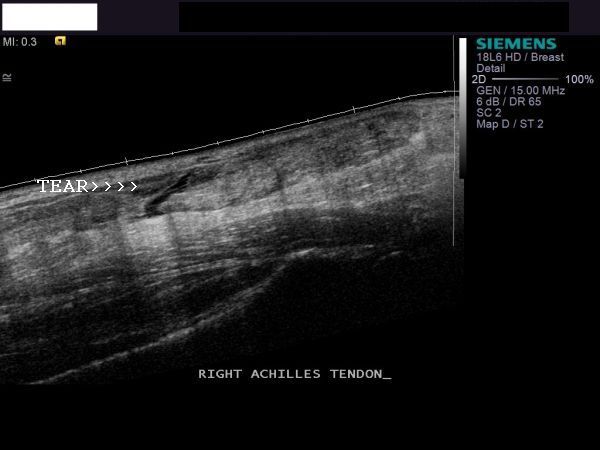

Rupture of the Achilles Tendon or Tendo achilles tear

This patient had severe pain in the lower calf. Ultrasound examination of the tendo-achilles showed a full thickness tear of the Achilles tendon. This is seen as the linear anechoic area extending through the tendon (long section ultrasound images of Achilles tendon). Transverse section (image on top left) shows fluid and blood around the tendon, seen as anechoic area. All above images are courtesy of Shlomo Gobi, Israel.